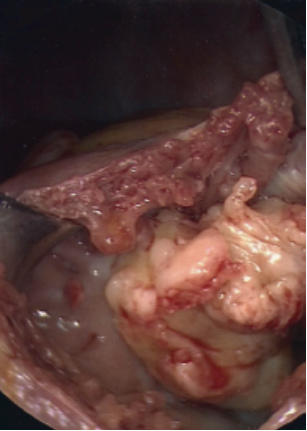

An 81-year-old man with a history significant for hypertension began to experience worsening shortness of breath, fatigue, and lower extremity edema. He was found to have a left upper lobe mass, but a biopsy was non-diagnostic. On further workup, a transthoracic echocardiogram (TTE) showed a large mass within the right atrium, which extended into the right ventricle (Figure 1). The patient had undergone a PET (positron emission tomography) scan, which showed +FDG (fludeoxyglucose) activity within the left upper lobe and mediastinum lymph nodes. The patient underwent a mediastinoscopy and bronchoscopy for tissue but both samples were non-diagnostic. The patient began to show signs of worsening right heart function with increased bilateral edema, elevated jugular venous distention, and complaints of worsening shortness of breath. Cardiac surgery was then consulted for tissue diagnosis and excision of the right atrial mass.